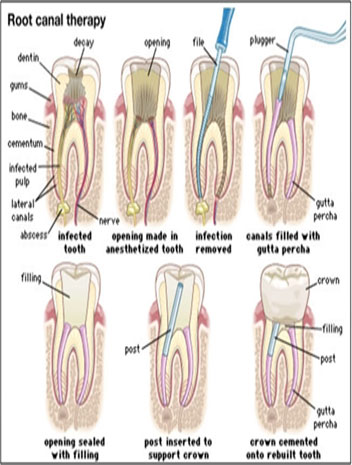

Endodontic therapy, also known as endodontic treatment or root canal therapy, is a treatment sequence for the infected pulp of a tooth which results in the elimination of infection and the protection of the decontaminated tooth from future microbial invasion.